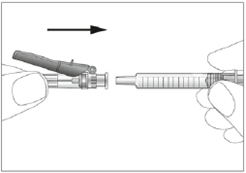

10. Setzen Sie die Nadel auf die Spritze auf (siehe Abbildung 3). Entfernen Sie noch nicht die Abdeckung von der Nadel.

3